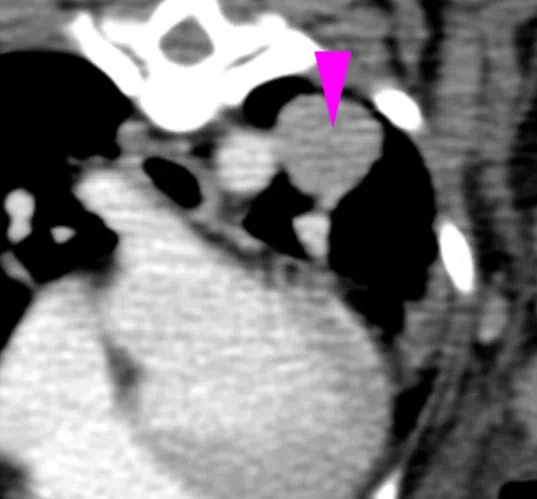

The tumour stayed at 1.7cm after Oscar underwent additional rounds of treatment.

PHOTO: NUS YONG LOO LIN SCHOOL OF MEDICINE

The dog had eight more treatment cycles ending in May 2022, when the tumour was found to have grown. Since then, it has shrunk slightly and has remained at 1.7cm. Oscar is now 14 and lives a normal life, with less frequent coughing and some asthma.

Dr Lee, Oscar’s vet, said: “That was one of the best outcomes we could expect from a lung tumour because it is typically quite aggressive and fast-growing.”